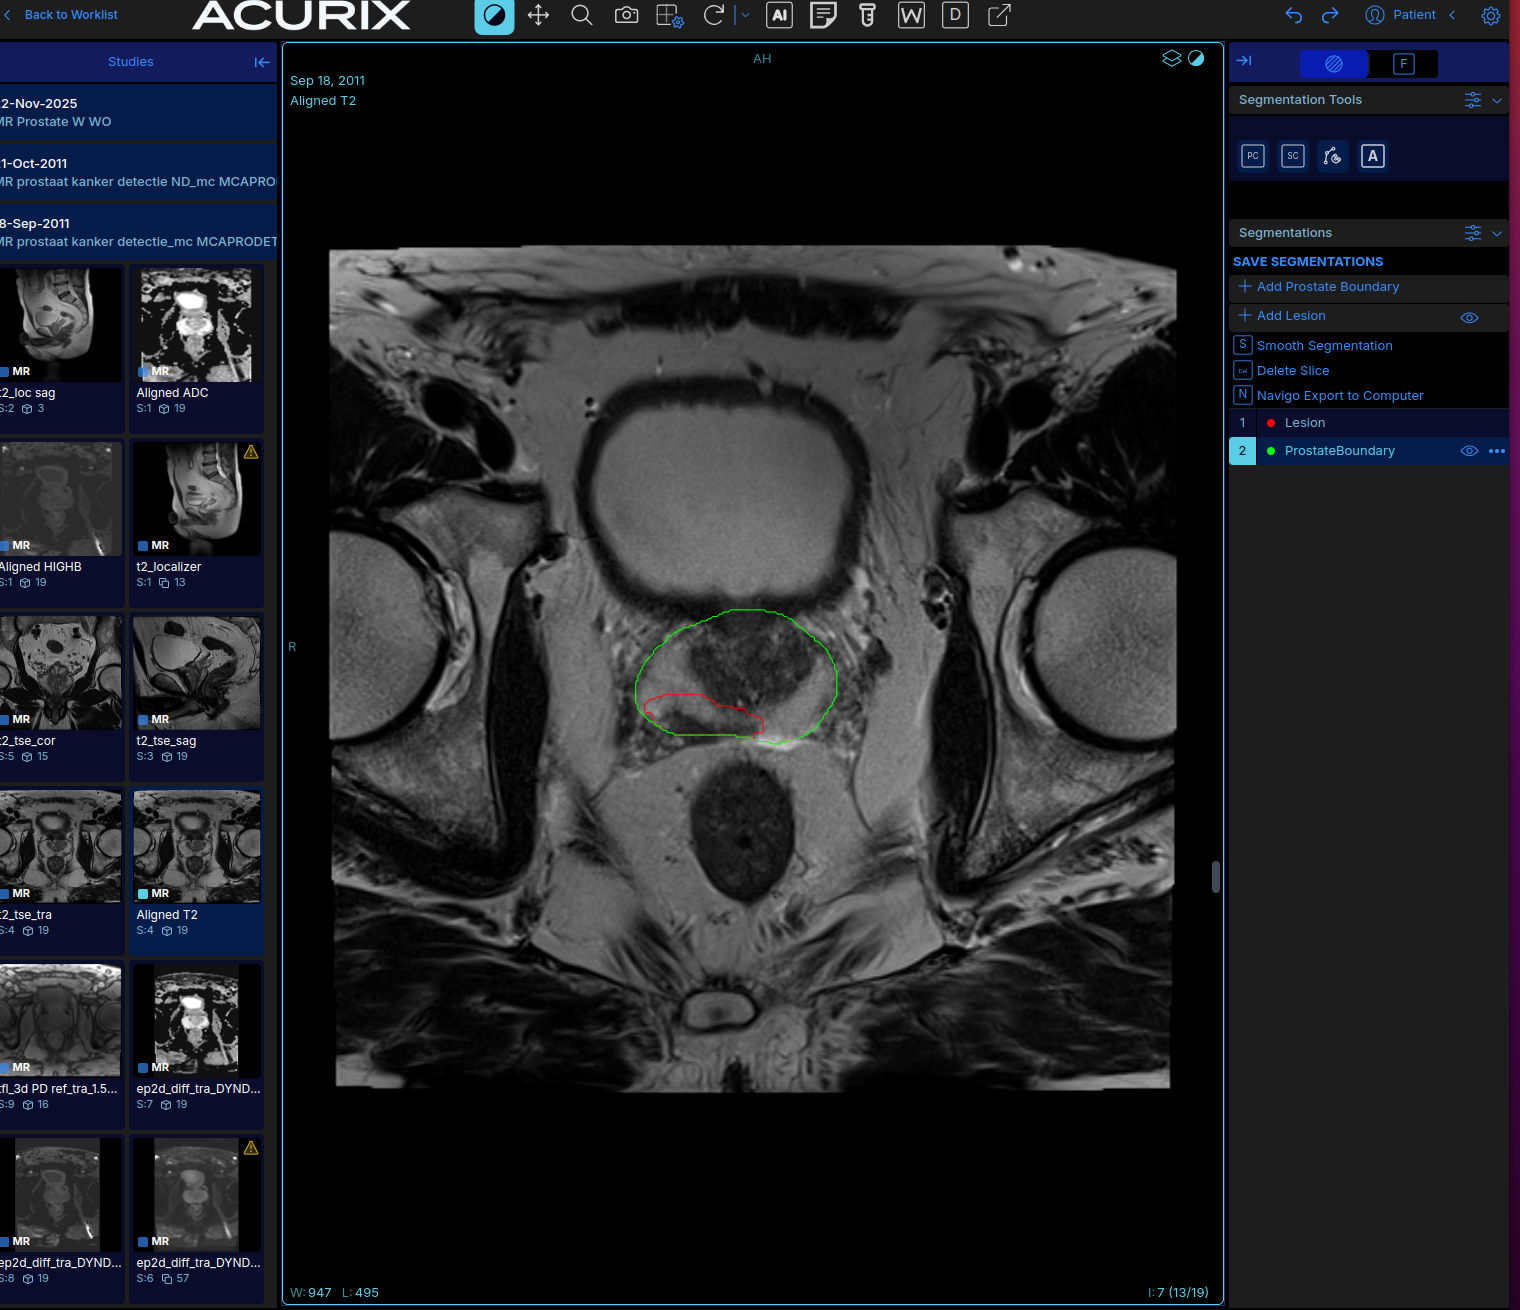

AI Segmentation & Lesion Detection

State-of-the-art deep learning models automatically segment the whole prostate boundary and transition zone, then identify candidate lesions. Contours are delivered as standard DICOM RTSTRUCT objects that can be edited directly in the viewer or exported to external systems.

AI-generated prostate boundary and lesion segmentation contours